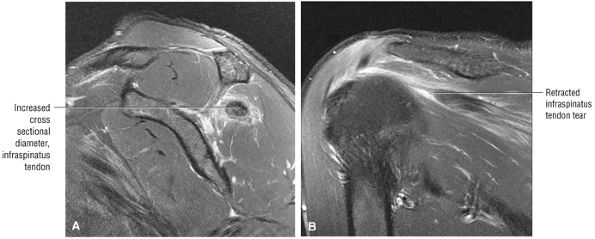

FIGURE 8.102 ● (A) The anterior undersurface of the acromion and the coracoacromial ligament form the coracoacromial arch. The subacromial subdeltoid bursa facilitates the passage of the rotator cuff and proximal humerus under the coracoacromial arch. (B) A superior axial image shows the anterior-to-posterior extent of the coracoacromial (CA) ligament perpendicular to the supraspinatus tendon. The fluid in the subacromial-subdeltoid bursa represents fluid between two serosal surfaces in contact with each other. One serosal surface is contributed by the undersurface of the coracoacromial arch and deltoid, and the other serosal surface is on the bursal side of the cuff.

|

![]() |